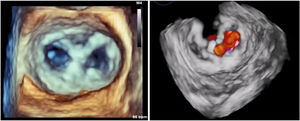

Se acordó implantar un MitraClip (Abbott Vascular, Estados Unidos) (figura 1) a una mujer de 79 años. Se obtuvo el consentimiento informado pertinente. Los intentos de punción transeptal (PTS), mediante una vaina Mullins y una aguja Brockenborough curvada manualmente en diversos ángulos, no dieron resultado debido a una pronunciada tortuosidad venosa. Los intentos de enderezar la vena cava inferior (VCI) con una vaina de calibre 14 Fr fueron infructuosos. Se utilizó entonces un catéter dirigible Agilis de curva media (St. Jude Medical, Estados Unidos) para alcanzar la fosa oval. Se realizó una PTS aplicando una breve descarga de energía de radiofrecuencia (∼ 60W) a una guía Confianza de 0,014” (Asahi Intecc, Estados Unidos). A continuación se introdujo la vaina Agilis en la aurícula izquierda (AI) y se colocaron 2 guías, Amplatz Superstiff y Extrastiff (Boston Scientific, Estados Unidos), en la vena pulmonar superior izquierda. Se retiró la vaina de 14 Fr y, tras dilatar el acceso venoso (18 Fr), se introdujo el catéter guía (CG) dirigible de 24 Fr sobre la guía Superstiff. Sin embargo, seguía siendo imposible atravesar el tabique interauricular (TIA) con el CG debido al poco apoyo y posibilidad de empuje en la VCI tortuosa. Se mantuvo el CG en la aurícula derecha y se introdujo una vaina de calibre 7 Fr sobre la otra guía (Amplatz Extrastiff). A continuación, se realizó una septostomía con balón de angioplastia transluminal percutánea de 10 × 40mm y, tras deshinchar el balón, se introdujo el CG de 24 Fr en la AI (figura 2). Por último, se colocó un MitraClip para tratar un prolapso A2-P2 (figura 3).